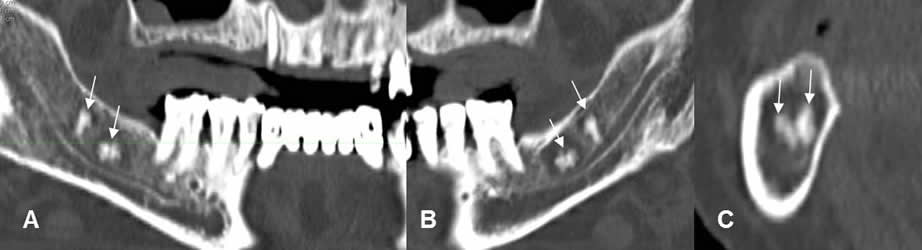

Fig 20 B. Raíces retenidas.

A y B: TAC reconstrucción panorámica y C: TAC reconstrucción coronal.

Ausencia de molares y premolares a nivel bilateral, con fragmentos de raíces retenidas.